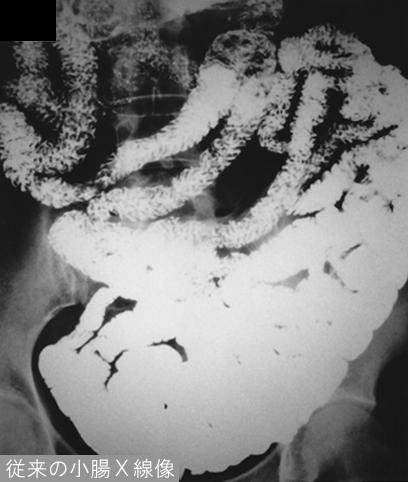

Posted by: Tokyo Pref., Cooperative study between National Cancer Center and Kyushu Cancer Center

[ Image ID:12147 ]